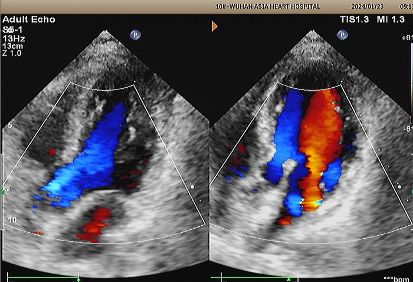

Implante: 2424 MemoSorb®Oclusor de PFO biodegradable desplegado bajo guía de eco y DSA.

Eco de 1 año:

No visible disc structures – replaced by 8mm tissue thickening at the septal implant site.

Zero residual shunt (rest or post-Valsalva).

Se ha confirmado la absorción completa del dispositivo.